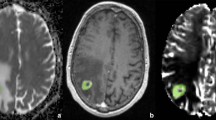

After visual inspection of the peritumoural rCBV changes on the parameter maps, a region of interest was defined by delineating an approximately 15-mm-wide rim outside the outer contrast-enhancing tumour margin (Fig. 1). These ROIs were adapted to the irregular shape of the tumour border excluding grey matter structures, pial arteries and venous structures as well as cerebrovascular fluid of ventricles and sulci. As a result, the rim of the ROIs could be focally smaller than 15 mm or even incomplete. The peritumoural ROIs were consensually overlaid by two neuroradiologists (S.B., E.H) onto the grey-coded rCBV maps using the imaging software ImageJ (http://rsbweb.nih.gov). ImageJ is a public-domain, Java-based graphical user interface developed at the National Institutes of Health, providing tools for calculating and reporting parameter means from marked areas, e.g. size of the ROI and mean rCBV for every ROI.

This figure shows the contrast-enhanced T1-weighted (a) and the grey-coded rCBV map (b) with the ROI placement in the peritumoural area and in the contralateral normal white matter (lower row). Please notice the increased rCBV values within rostral and lateral rim of the peritumoural ROI (b, lower row) of a GBM

The peritumoural rCBV values were expressed as ratios to the rCBV of an at least 30-mm2 area in the contralateral normal-appearing white matter, normalising CBV to an internal reference (Fig. 1). This approach has been shown to provide the best interobserver and intraobserver reproducibility in previous studies [18, 36].

The results of the present study indicate that peritumoural rCBV is feasible to discriminate metastases from GBM. The cutoff value of 1.0 for the peritumoural rCBV values yields a high negative predictive value and a high specificity to detect metastases. The threshold of 1.0 was found to be optimal by another study investigating solitary brain tumours in the region of maximal rCBV [37]. We used this cutoff value following the concept that tumour cell infiltration beyond the contrast-enhancing tumour border induces rCBV increase, and hence rCBV increase should be detected in the peritumoural area of GBM (Fig. 1), but not of non-infiltrating metastases (normalised rCBV value related to rCBV value of normal-appearing brain tissue ≤1.0). However, peritumoural rCBV decrease was found in both metastases and in GBM (Figs. 4 and 5). Visual inspection of the rCBV parameter maps was even more sensitive in delineating peritumoural rCBV increase because averaging heterogeneous rCBV values of all voxels within a ROI may equalise small areas of rCBV increase. However, we performed the ROI method to get a more objective analysis.